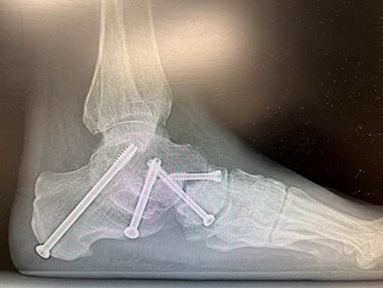

Some months ago, when I last wrote in this space I was recovering from extensive foot surgery. I ended up with 4 screws in my left foot, 14 weeks of non-weight-bearing status, and many months of rehab. While I was able to continue with my day-to-day activities as a lawyer, physical activities were very limited.